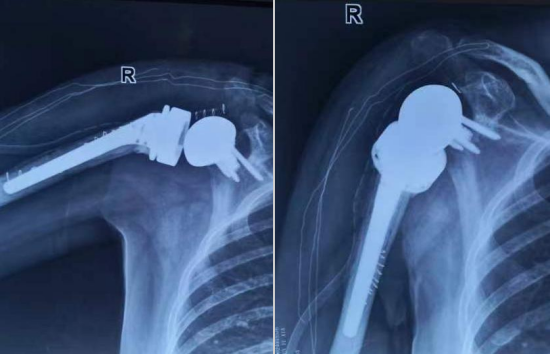

术后影像

王文波对李女士右肩关节进行彻底清创手术,术后患者的感染很快得到治愈,但右臂功能严重受限。王文波团队择期为患者行二期反向全肩关节置换术,最大程度保留肩关节活动度,恢复李女士的肩关节活动度及稳定性。术后,经过康复训练,李女士已能自主完成洗脸洗头、刷牙喝水等基本的日常活动。

王文波介绍,反向全肩关节置换术能有效恢复肩关节活动度及稳定性,适用于难治性巨大肩袖撕裂、肱骨近端粉碎性骨折、肩关节感染或创伤后骨关节炎、肱骨近端骨肿瘤等疾病的晚期功能重建。与其他手术方式相比,反向全肩关节置换术能很大程度保留肩关节活动度,提升患者生活质量,是患有严重肩关节疾病患者最合理的治疗选择。